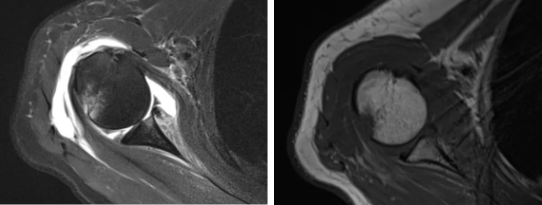

病例1

病史摘要:男性,44歲,跌傷致右肩關(guān)節(jié)疼痛數(shù)天,活動(dòng)不利。

MR圖示:右側(cè)肱骨后外上方局部骨皮質(zhì)塌陷,并鄰近皮質(zhì)下斑片狀壓脂高信號(hào)影(箭頭);前盂唇撕脫,前方見(jiàn)低信號(hào)游離骨片影(三角形)。